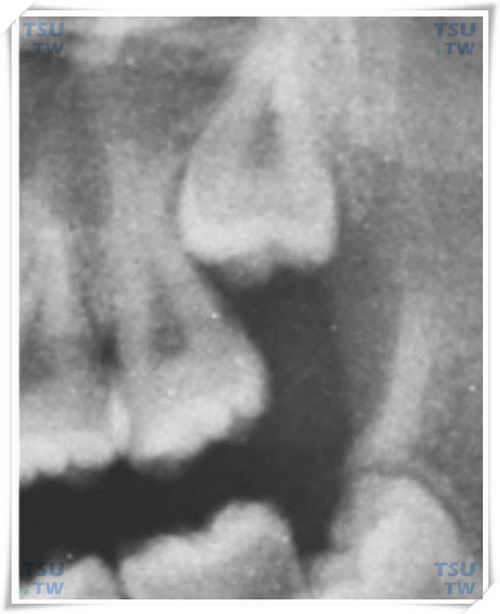

3倒逆是指上下颌智齿冠部向相反方向萌出生长的智齿,其智齿处在埋伏在颌骨内不能够萌出的状态。上颌倒逆阻生智齿是指智齿的咬合面朝向上方,见下图。上颌间位远中倾斜高位阻生智